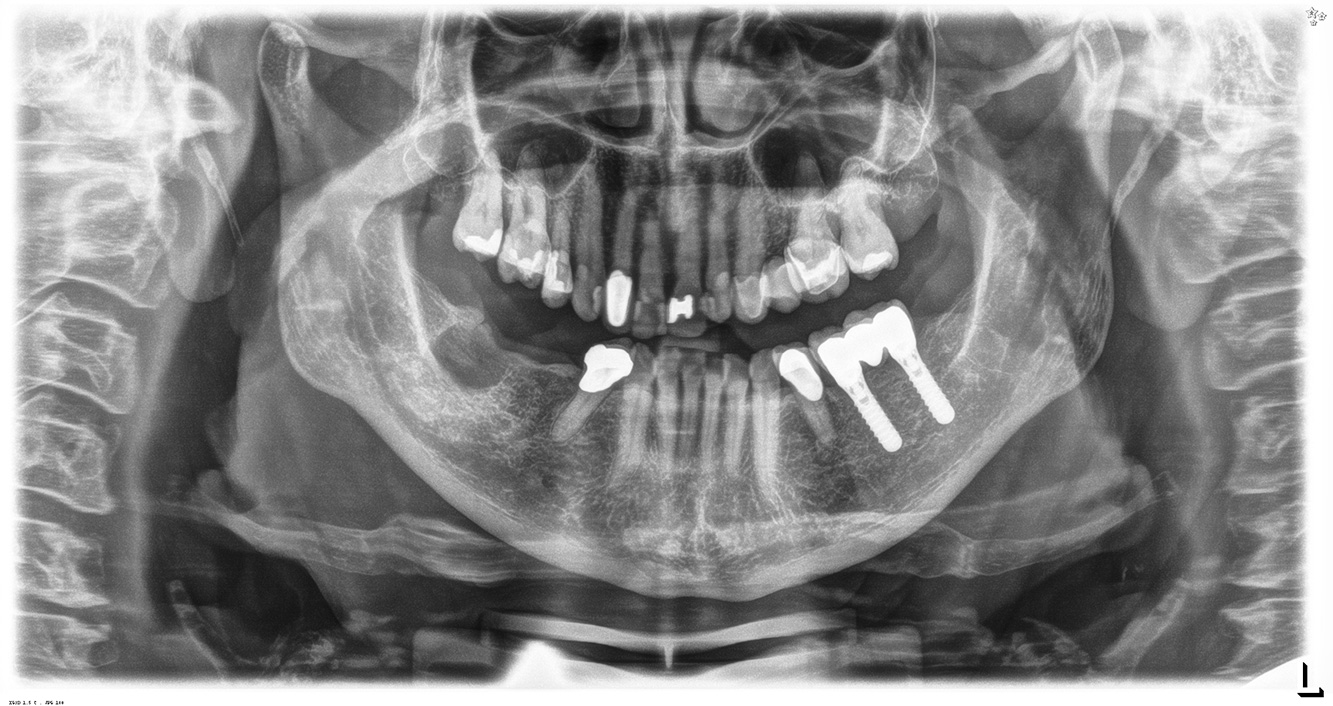

Questa paziente di 68 anni non presenta alcuna patologia precedente né segue alcuna terapia che possano ritenersi rilevanti dal punto di vista odontoiatrico, e il suo stile di vita non comporta alcun rischio particolare. La paziente ha due impianti (3° quadrante, da cinque anni) e una precedente patologia parodontale (parodontite allo stadio IV, grado B) con perdita del dente. Al momento le condizioni parodontali sono stabili, tuttavia la parodontite aumenta in misura significativa le complicazioni biologiche degli impianti e c'è dunque il rischio di perdita dell'impianto (21). Per la seduta di profilassi si possono formulare quattro consigli.

Siccome la paziente non presenta alcun fattore di rischio particolare con specifiche implicazioni odontoiatriche, i bisogni rilevati dal suo attuale stato

di salute orale sono determinanti. In questo caso, si consiglia una valutazione accurata della condizione parodontale una volta l'anno. In questo modo si ha la certezza di poter intervenire in tempo qualora la precedente patologia parodontale dovesse progredire o si sviluppasse una perimplantite.

Siccome la paziente ha impianti e una malattia parodontale precedente, è a rischio di sviluppare una perimplantite. È pertanto consigliabile fissare

una seduta di richiamo ogni tre-quattro mesi.